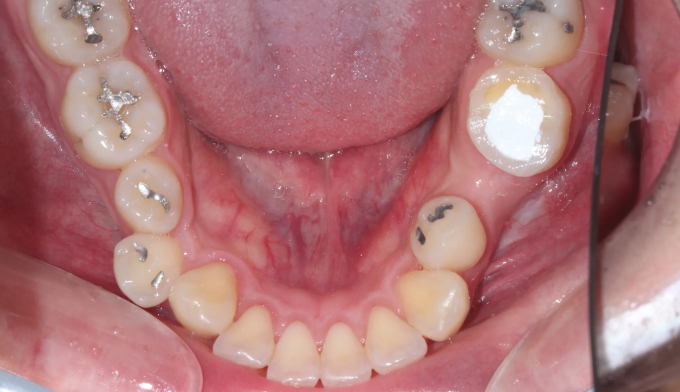

돌출감과 가지런하지 못한 앞니, 그리고 어금니의 교합이 좋지 않은 경우입니다.

좌측 아래 작은어금니가 빠진이 오래되었기 때문에, 균형을 맞추기 위해 반대편 작은어금니를 발치하여 돌출감을 해소해주었습니다. 나왔던 입이 들어가면서 턱 라인이 개선되었고, 입을 다물때도 보다 더 편안하게 되었습니다.

교정전부터 변색되어있던 양쪽 앞니는 미백과 보철치료를 동반하여 교정종료 후 개선하였습니다.

총 교정치료는 22개월입니다.